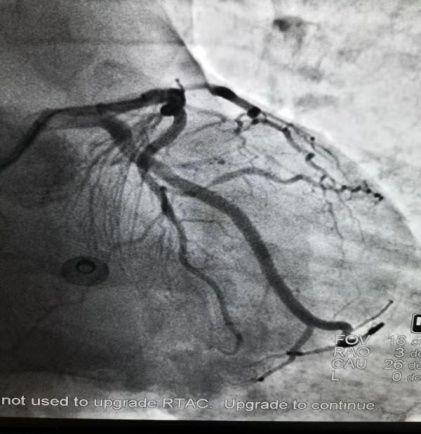

患者实例最近急诊室遇到一名49岁中年男性患者,因胸闷2小时来院,无胸痛。急诊室查心电图、心肌酶基本正常。给予留观,两小时后复查心电图变化不明显,但是心肌酶轻度异常,考虑存在急性冠脉综合征可能,建议急诊行冠脉造影检查帮助诊断。在取得患者及家属同意并且签署同意书后,急诊冠脉造影检查。

结果一出,术者惊出一身冷汗,我的天呐:三支冠状动脉全部病变:回旋支闭塞,前降支、右冠重度狭窄!

/术前/

追溯病史,患者中年男性,无烟酒嗜好,多年前发现血糖升高,未予重视,没有正规诊断及治疗,急诊室测随机血糖17.1mmol/L,无其他危险因素。